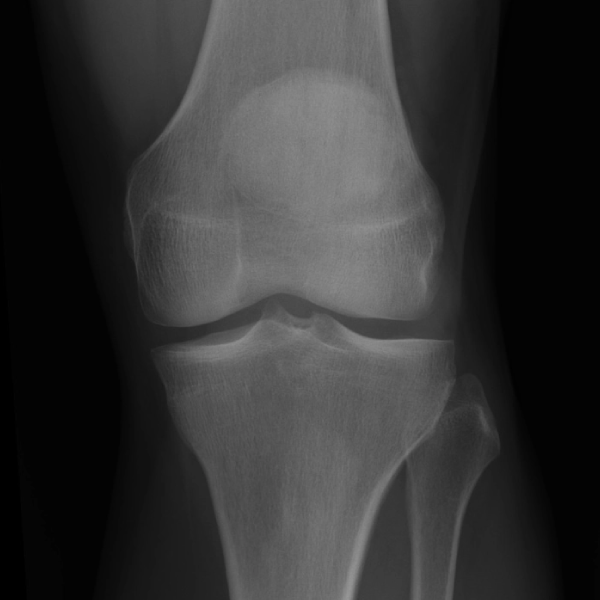

Learn the bony anatomy then test yourself

Learning mode: Hover over the name tags to highlight the relevant anatomy. Once you're ready, head to study mode.

Study mode 1: Click the correct anatomy to match the tag presented.

Study mode 2: Click the correct tag to match the anatomy highlighted.